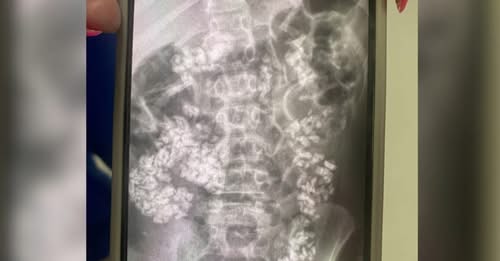

“We were not expecting what we saw when we got the X-ray at all,” she said.

When Whitlow was shown her son’s abdominal X-ray, she says she saw large amounts of gravel throughout his intestinal tract, terrifying her. While the 9-year-old was able to go home that night, she originally wasn’t sure that would be the case. Doctors spoke to Whitlow about possibly taking her son to Cardinal Glennon Children’s Hospital in St. Louis.